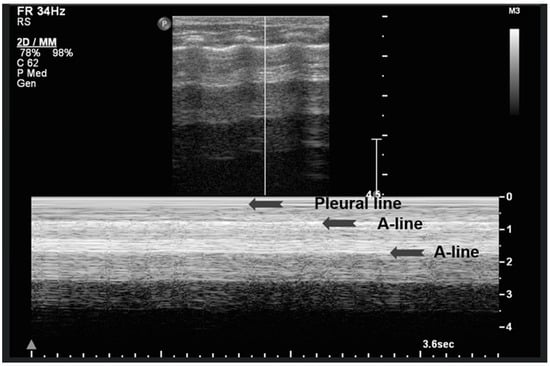

A-lines are horizontal, bright, echogenic lines that appear at equal intervals below the pleural line, running parallel to it (Figure 1). They are reverberation artifacts caused by the reflection of ultrasound waves between the pleura and the ultrasound probe. Although their presence typically indicates well-aerated, healthy lung tissue, A-lines can also be seen in certain pathological conditions, such as pneumothorax, where free air is present. Thus, A-lines are not always necessarily a sign of normal, healthy lungs [5,6,12,13,14,15,16].

A-lines: Horizontal, bright, echogenic lines at equal intervals below the pleural line, running parallel to it. A-Lines are one of the main (basic) artifacts in LUS.

Figure 6.

Upper image: LUS with normal A-Lines in B (bright)-mode. The simultaneous M (motion)-mode image (lower image) reveals series of horizontal echogenic lines which represent the pleural line and its reverberations (A-lines), as well as the air-filled alveoli with a granular/sandy appearance (more prominent in real time scan). These in combination produce the seashore sign.

In contrast, the underlying lung parenchyma, which moves in synch with respiration, generates a granular or sandy appearance due to the dynamic motion of air-filled alveoli [17]. This combination creates the visual effect of waves (static layers) above and sand (with a dynamic speckled texture) below, thus producing the so-called “sea-shore sign”. The presence of this sign confirms normal apposition and movement of the visceral and parietal pleurae, and can be used to effectively rule out pneumothorax at the examination site. The “sea-shore sign” is considered to be a reliable and non-invasive indicator of intact lung sliding, and is frequently used in both adult and neonatal lung ultrasound to assess respiratory function and pleural integrity [5,6,15,22,23].